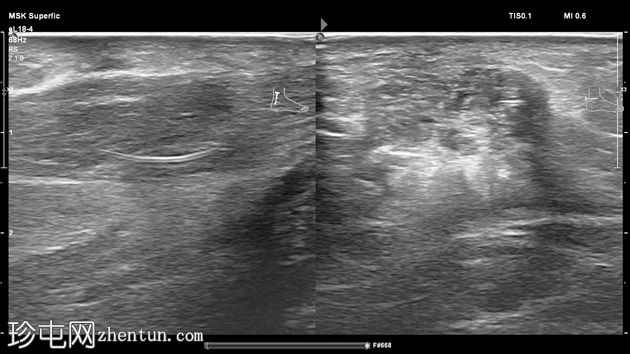

纵位

横位

纵位和横位

左足跟皮下组织内可见一管状高回声物质,呈串珠状,与手术缝线相符,周围环绕着低回声积液。与缝线相连的是一根细细的、呈轨道状的高回声合成单丝,它穿过跟腱呈弧形走行,该缝线为不可吸收缝线。